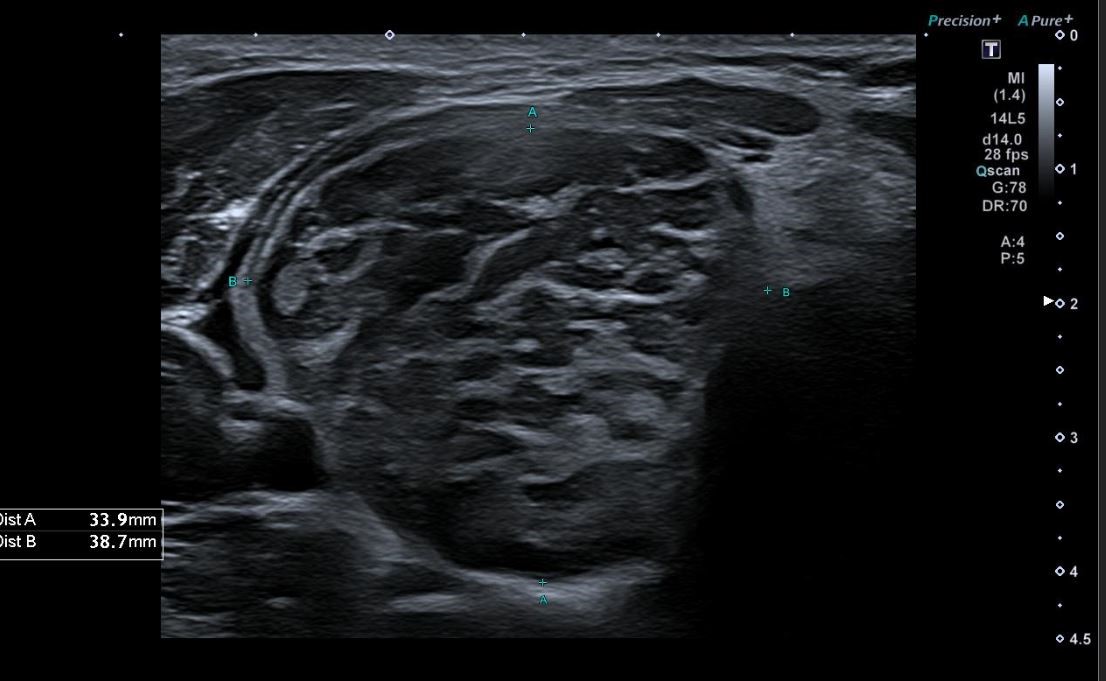

Una vez realizada la anamnesis y la exploración física, se decide realizar una ecografía clínica en la consulta, donde se objetiva un aumento difuso de tamaño del lóbulo tiroideo derecho (33,9 x 38,7 mm), levemente hipoecogénico, con áreas anecoicas en su interior y adenopatías asociadas. Se aplica Doppler color resultando positivo.

El juicio clínico es de una tiroiditis aguda, por lo que se deriva al paciente a urgencias hospitalarias. En urgencias se solicita una analítica sanguínea en la que destaca Leucocitos 7,34 x 103 y PCR 68 mg/L; y una ecografía reglada donde se informa de «tiroides aumentado de tamaño a expensas de lóbulo tiroideo derecho con alteración de la ecogenicidad del parénquima que sugiere proceso infiltrativo afectado al lóbulo derecho, istmo y región anterior del lóbulo izquierdo, no pudiendo apreciar etiología infiltrativa o tumoral».